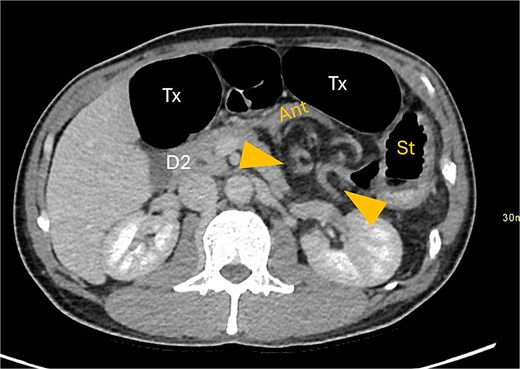

A contrast-enhanced computed tomography (CT) scan of the abdomen and pelvis demonstrated a large bowel obstruction with a transition point at the distal transverse colon with swirling of the mesentery. Downstream large bowel was collapsed. Upstream dilatation included the terminal ileum suggested an incompetent ileo-caecal valve. The gastric antrum was also involved in the internal hernia, resulting in gastric outlet obstruction. See Figs 1–5.

Axial CT image demonstrating distended transverse colon (Tx) and stomach (st).

Gastric outflow obstruction of stomach (st) from compression of antrum (ant) by herniated transverse colon. Hernia between arrows.